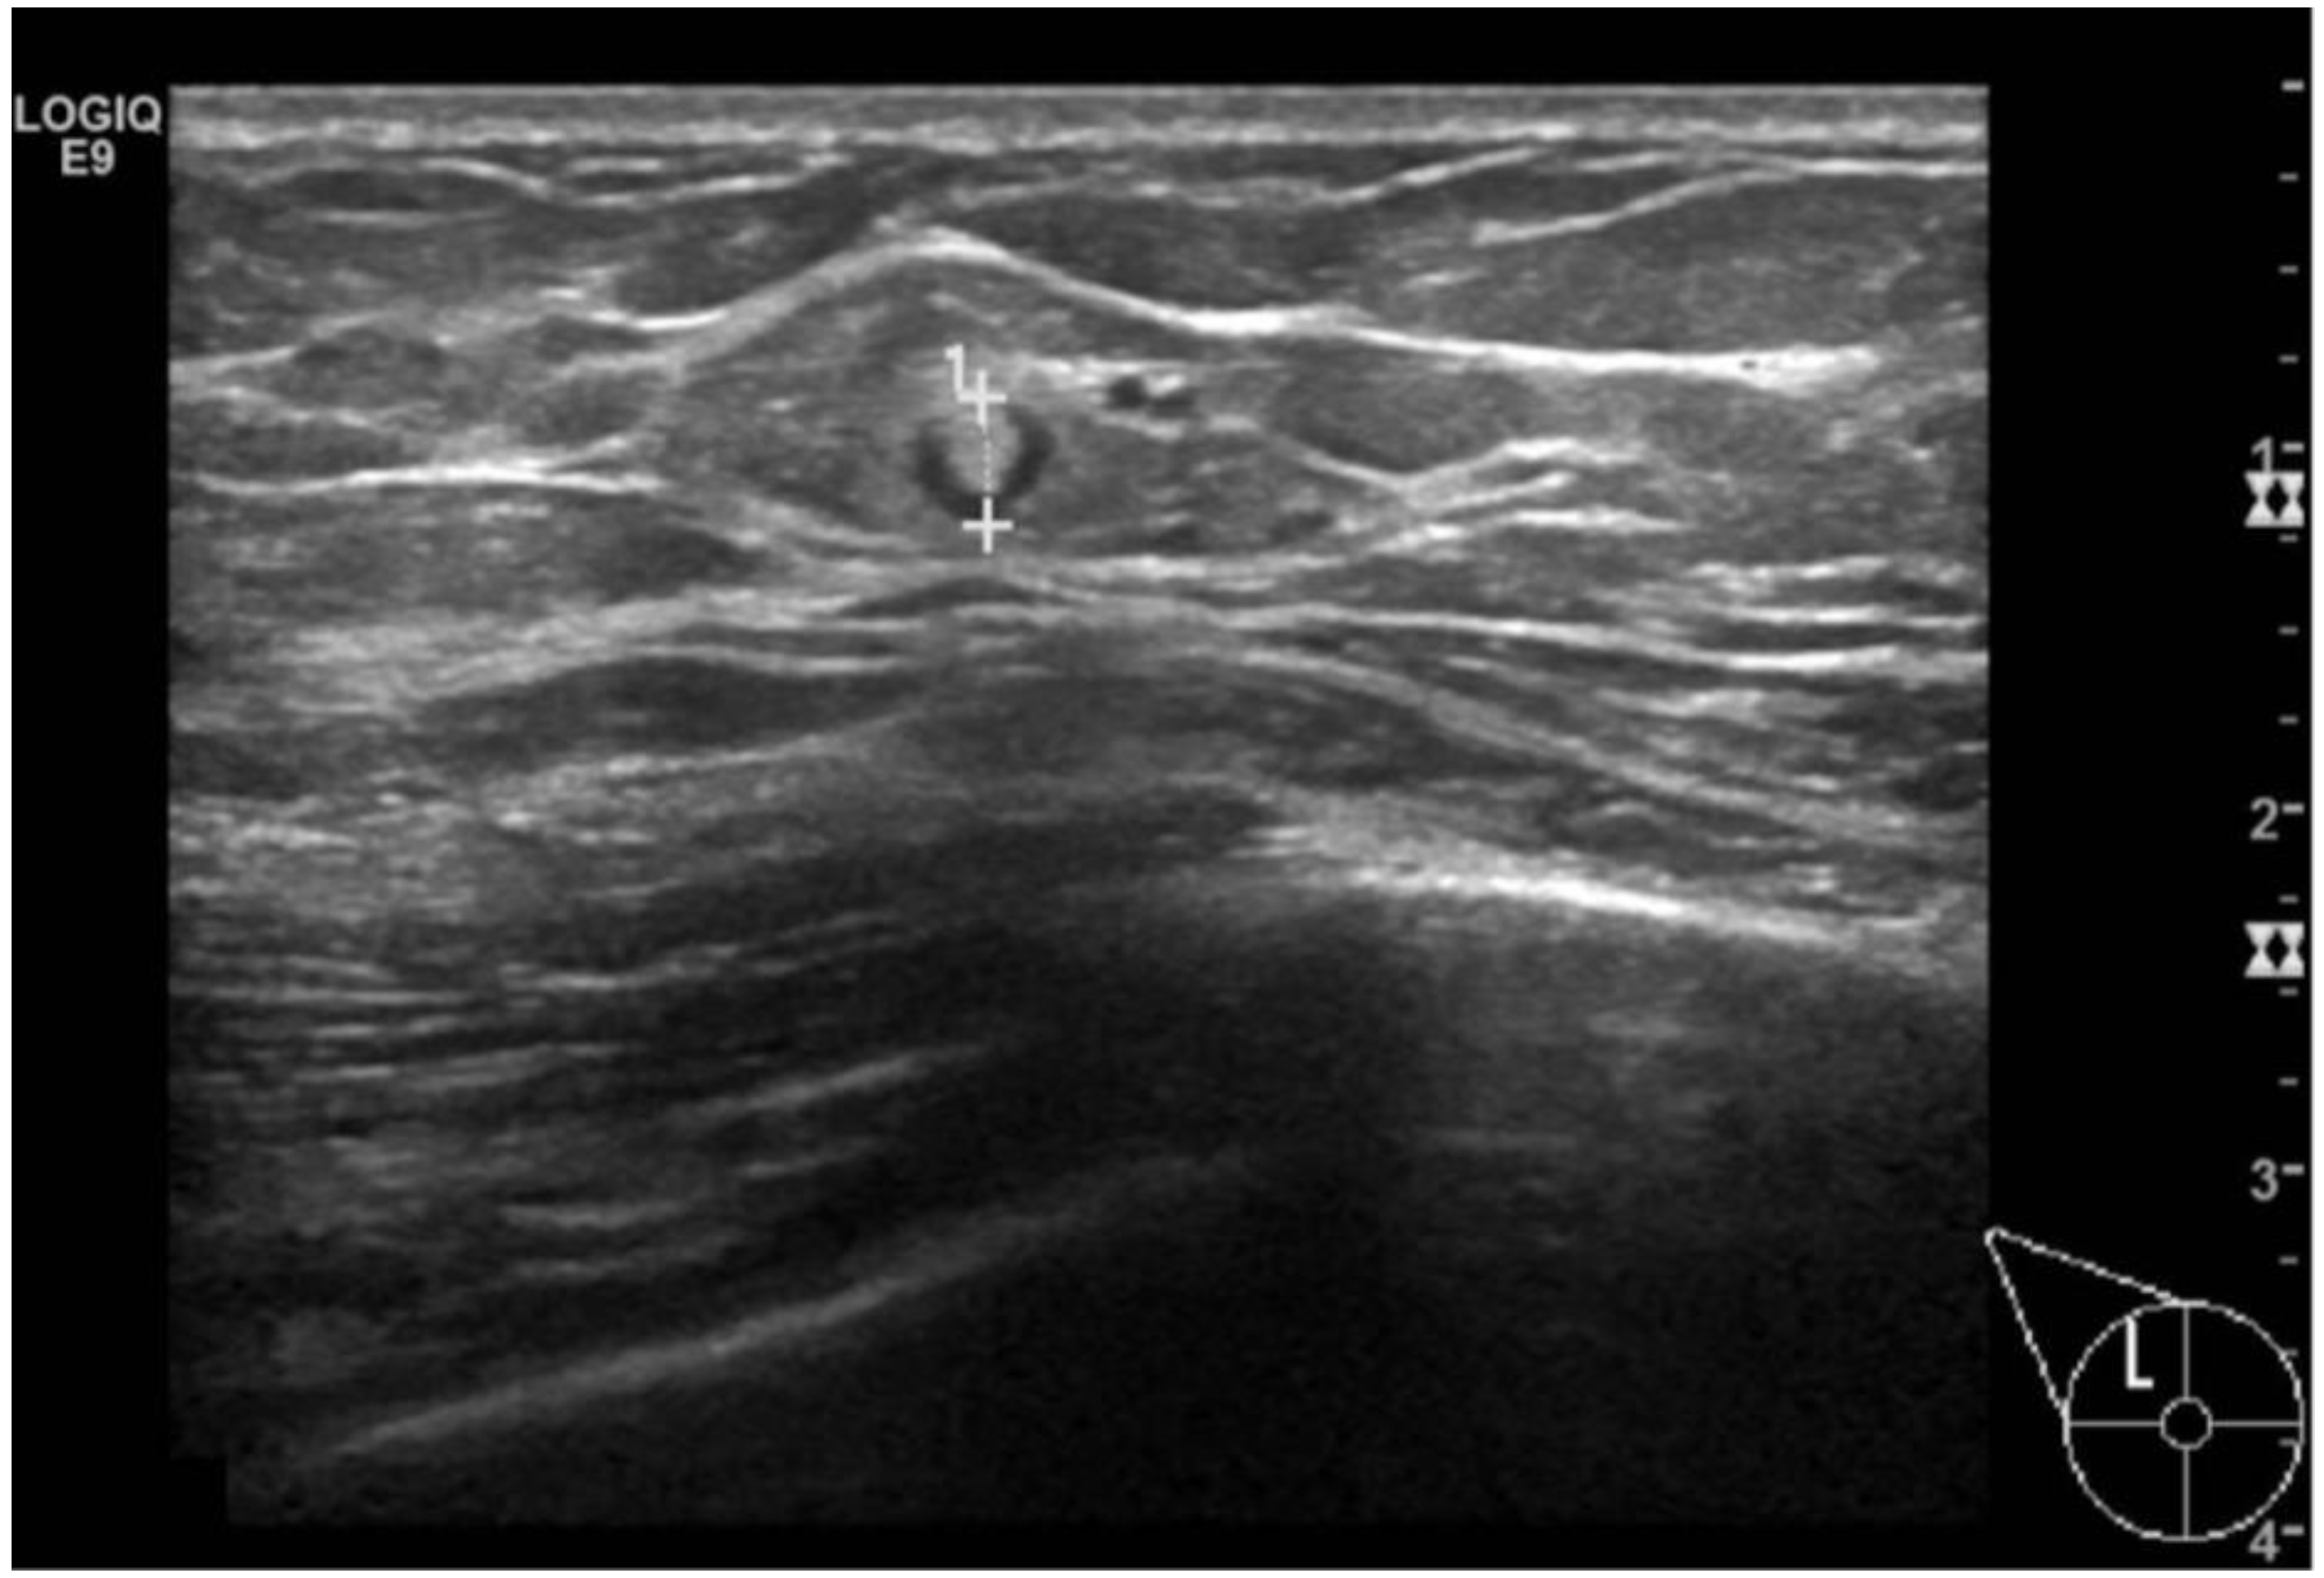

Lipomas, the second most common benign lesions in the MB, are composed of adipose tissue and typically present as soft, mobile, and palpable masses in clinical examination. However, they are frequently detected incidentally. Mammographically, lipomas appear as well-defined radiolucent oval masses with a radiopaque capsule that might be difficult to detect [14,15]. On ultrasound, lipomas demonstrate an oval shape, parallel orientation, iso-hyperechoic echogenicity, and lack detectable vascular flow [16] (Figure 3).

Figure 3.

A 35-year-old men with a palpable lump in the inner quadrants of the left breast. On a B-mode (A) breast ultrasound, there is an oval shaped and hyperechoic mass, with circumscribed margins and parallel orientation. No posterior feature is associated. On color-doppler (B), there are no signs of vascularization. The imaging features are consistent with a lipoma.